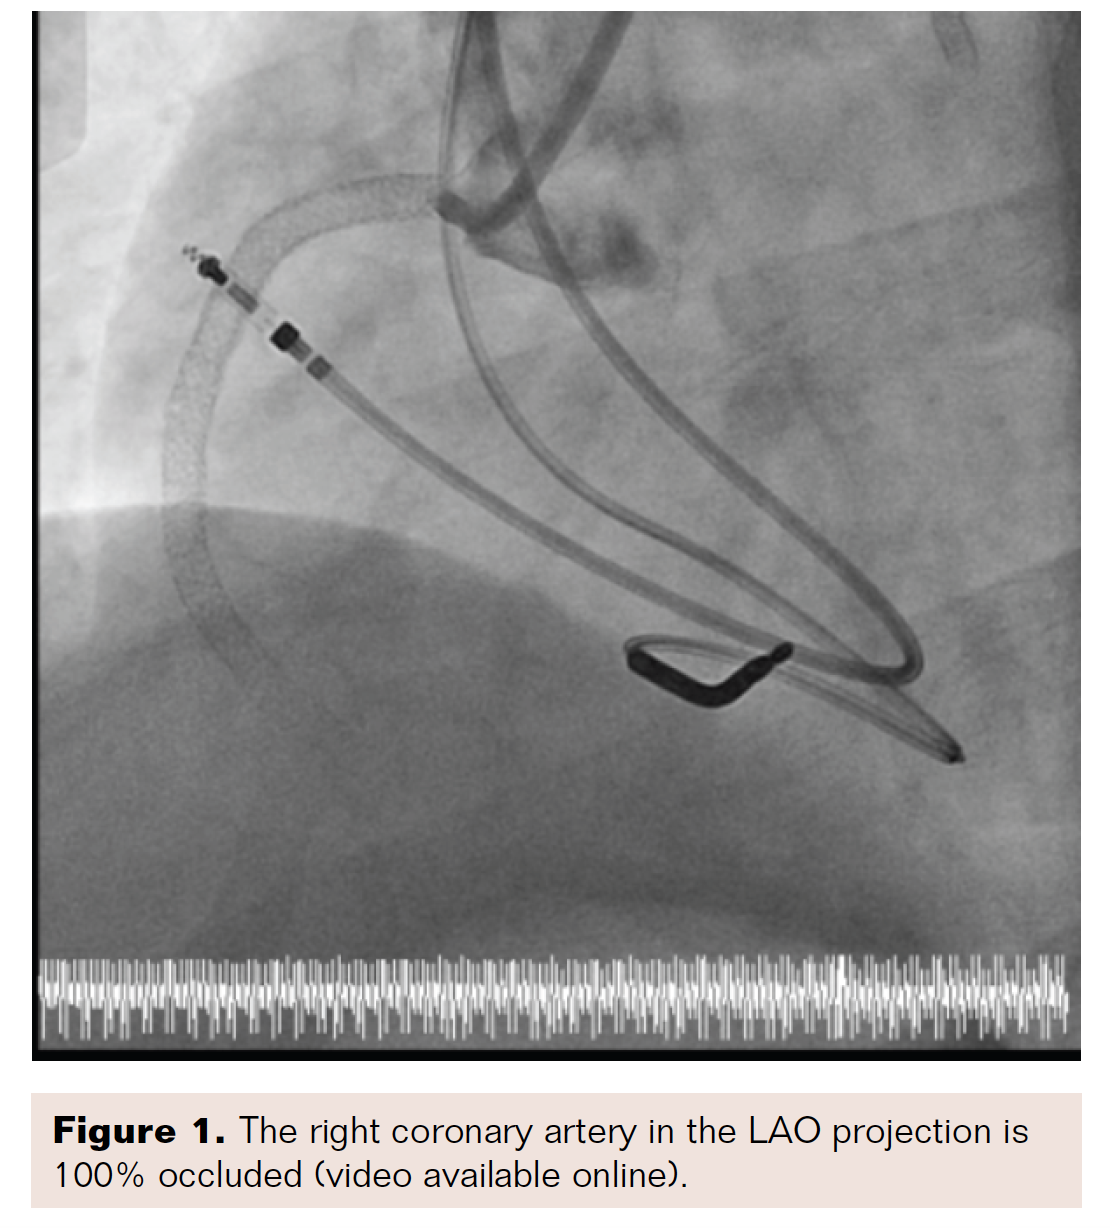

We entered from the right groin, and, using an 8 French right coronary artery Judkins guide catheter (Medtronic), passed the CrossLock device, as well as an 0.9 mm excimer coronary laser angioplasty (ECLA) catheter (Philips), and a Miracle 3 wire (Asahi Intecc). After entering the proximal third of the chronic total occlusion (CTO), we switched to a 7 French Amplatz guide catheter (Boston Scientific) and a Fielder XT guidewire (Asahi Intecc) (Figure 2). With the Fielder, we were able to travel approximately halfway across the vessel and address the lesion with the laser. We then passed the Whisper wire (Boston Scientific) into the posterior branch of the RCA, completely recanalizing the CTO (Figure 3). After recanalization, we performed balloon angioplasty with a 1.5 mm Somerset balloon (Terumo), followed by a 4 mm balloon in the proximal portion of the in-stent restenosis (Figures 4-5).